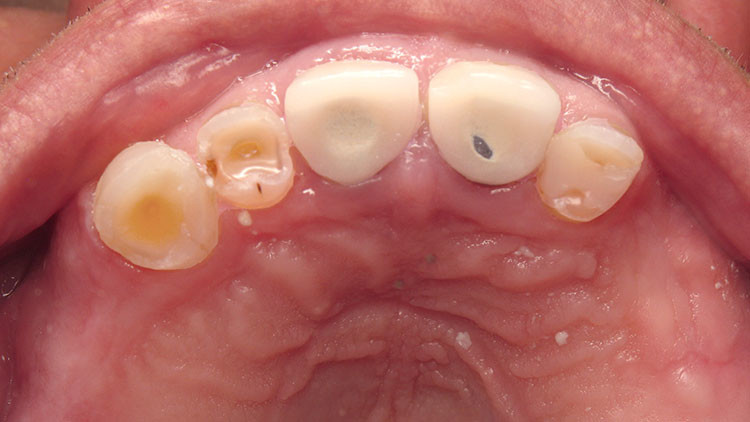

Occlusal hypervigilance can take a number of forms. Some patients become exquisitely sensitive about the way their teeth meet to the extent that they are better at detecting interferences than many dentists. These patients appear to have an amplified level of sensation which can be troublesome when perceived as pain. Nevertheless, unlike the princess and the pea, there is often a heavy occlusal contact present — you just need to know how to look for it and adjust it. A pitfall of not recognising such a patient is unnecessary root canal treatment.